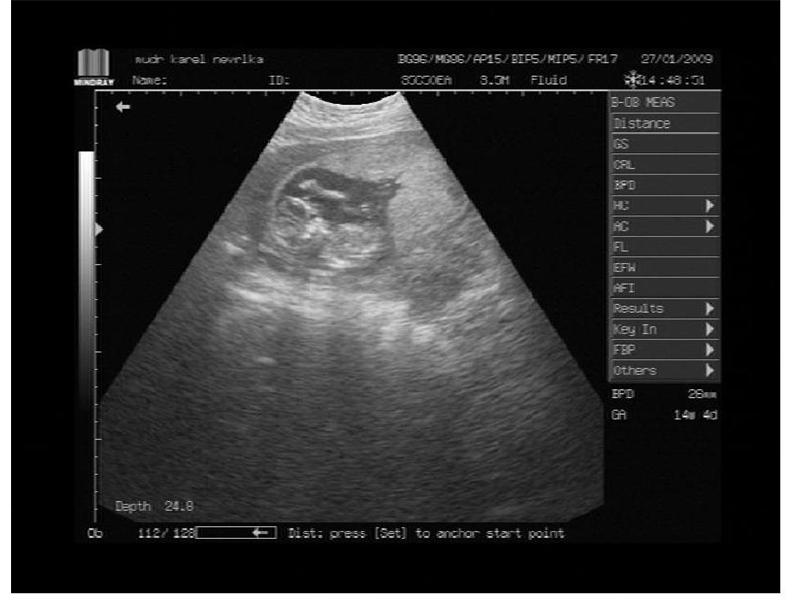

mává ručičkou a je vidět i paleček